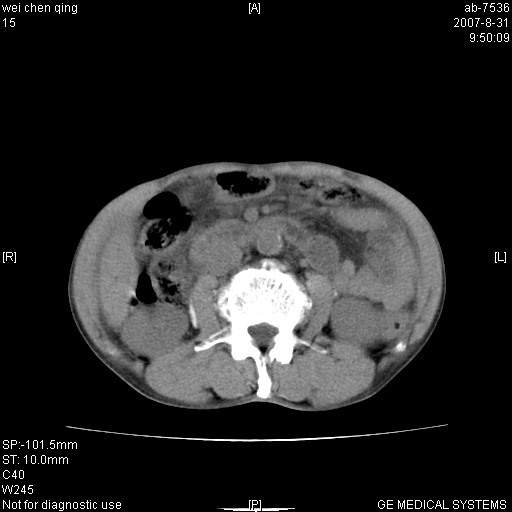

以下是引用zyyzzy在2007-8-31 14:34:00的发言:[br]该病人肝内胆管扩张,胆囊及胆总管未见明显扩张。在倒数第9层图像上可看到左右肝管结合部(肝总管)有软组织影,此处应薄层扫描。考虑肝总管占位(ca)、腹水。[br]